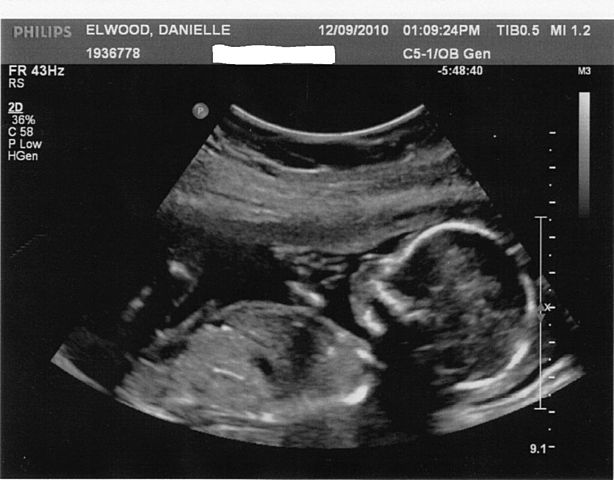

• tercera ecografia

tercera ecografia

esta fue realizada a los 8 meses y se le comunica a la mama que el bebe esta en perfectas condicione y que esta bien ubicado asi que los mas probable es que su nacimiento va ser por parto natural